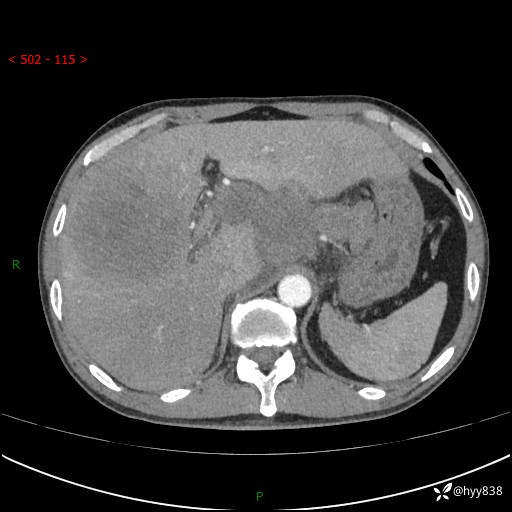

上腹部CT平扫+增强(两期)